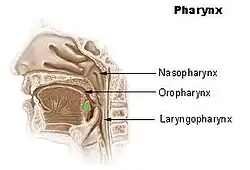

Keratosis Pharyngis is a medical condition where keratin grows on the surface of the pharynx, that is the part of the throat at the back of the mouth.[1] Keratin is a protein that normally occurs as the main component of hair and nails. It is characterized by the presence of whitish-yellow dots on the pharyngeal wall, tonsils or lingual tonsils. They are firmly adherent and cannot be wiped off.[1] The surrounding region does not show any sign or inflammation or any other symptoms that make affect the rest of the body.